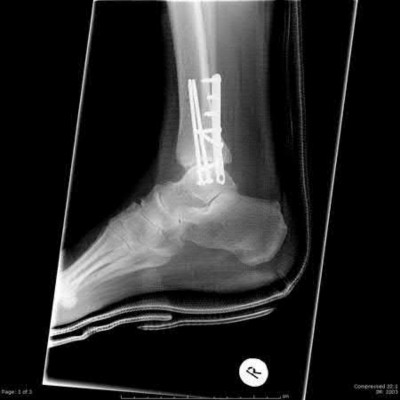

Slide 1

A 23-year-old carpenter fell off a roof 4 weeks ago. He has pain in the ankle and a deformity. The lateral radiograph is presented (Slide). Which of the following treatments is most likely to return this patient to work with a functioning foot and ankle: